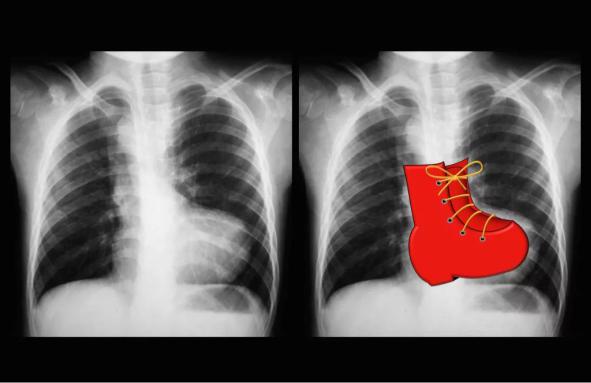

При некоторых врожденных пороках сердце имеет характерную конфигурацию, например при тетраде Фалло – «деревянный башмачок», или при транспозиции магистральных сосудов – «яйцо, лежащее на боку»:

Характерная конфигурация, например при тетраде

Фалло – «деревянный башмачок», или при транспозиции магистральных сосудов – «яйцо, лежащее на боку»